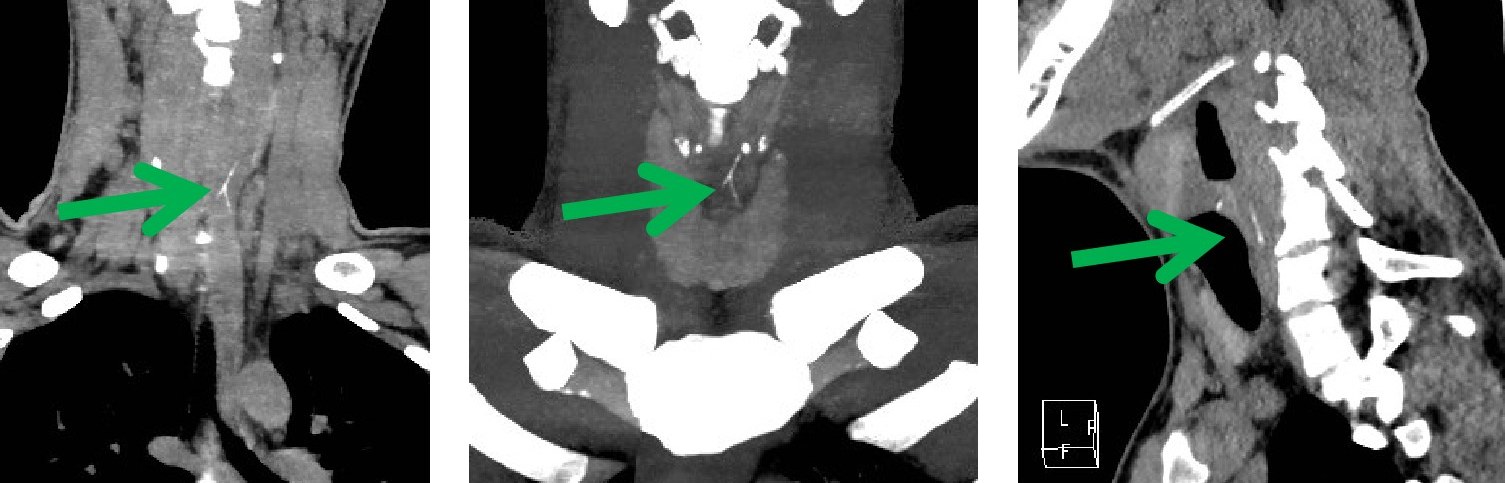

近日,我科来了一位十九岁的患者,一小时前吃鱼,一个不小心,把鱼刺咽下去了。感觉咽部不适异物感,急忙来医院就诊。先进行了喉镜检查 ,没有发现鱼刺的踪影。便连忙来到我科,进行食管异物CT扫描。此时,我科医生的火眼金睛该登场了,果然一下子就发现了罪魁祸首——狡猾的鱼刺。在患者的颈6椎体平面食道内,我们看到一个倒“Y”形的高密度影。我科医生又通过计算机后处理技术,很快这根鱼刺既直观又立体的展现在我们的眼前,鱼刺你终于藏不住了吧!

CT薄层重建图像结合后处理技术能多平面、多方位观察及定位,了解异物与食管壁、周围组织间的关系与损伤程度,主要重建方法包括多平面重建 (multiplanar reconstruction,MPR)、最大密度投影 (maximum intensity projection,MIP) 及容积再现 (volume rendering,VR)。

MPR、VR 及 MIP 多种重建方式的联合应用可对食管异物及早诊断,确定异物大小、形态、走向及位置,能多角度、任意方位地对组织器官进行观察和分析,直观、立体显示异物与周围组织结构的关系及有无并发症,为临床治疗方案的选择提供较大的指导意义,是诊断食管异物的可靠方法,已经成为食管异物诊断的首选检查方法。